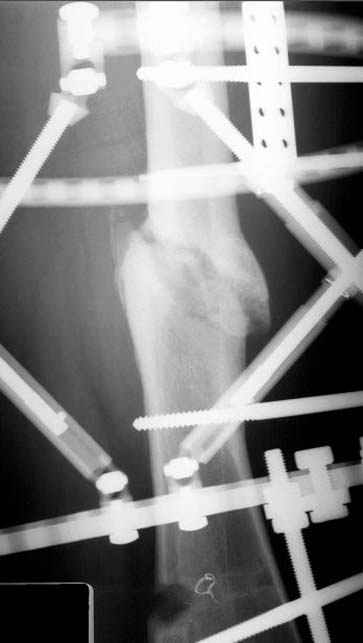

Несколько снимков из моей коллекции, чтобы разьяснить, почему мы до сих пор делаем различные варианты остеотомии.

На рисунке N1 предоперационный план лечения ложного сустава шейки бедра- линия ложного сустава, угол и направление введения импланта, клиновидная остеотомия в градусах и миллиметрах, второй снимок после коррекции, расчет, на сколько удлиняется конечность и размеры импланта;

N3 рисунок окончательный снимок, после операции моя рентгенограмма должен выглядеть примерно как эта картина. На N4 снимке клин перед удалением; N5 послеоперации 3 нед.; N6 окончательная рентгенограмма.

Отправитель: Djoldas Kuldjanov 23 Ноябрь 2004, 18:21

пластическая модель; и коррекция бедра аппаратом Илизарова.